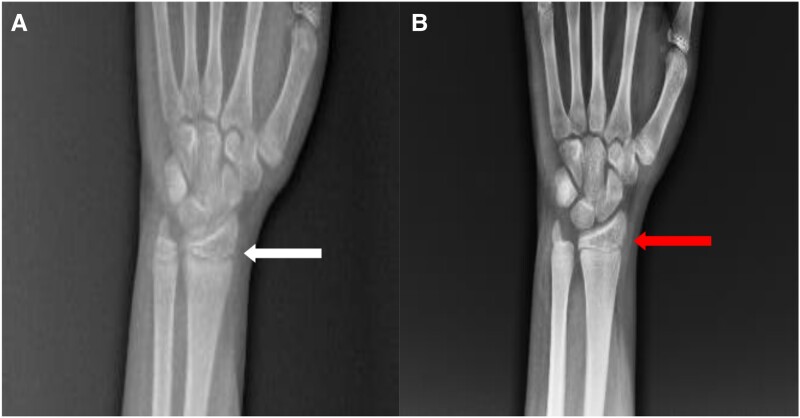

Vitamin D-dependent rickets type 1A is caused by pathogenic variants of CYP27B1 gene, which is inherited in autosomal recessive pattern. These variants lead to defective 1α-hydroxylase enzymatic activity, leading to impaired renal formation of 1,25(OH)2 vitamin D. We report a case of a 16-year-old Asian male patient, with short stature and progressive bone deformity, whose biochemical parameters revealed low levels of 1,25(OH)2 vitamin D, low serum calcium levels, along with high phosphorus and raised levels of intact parathyroid hormone. These biochemical parameters suggested the diagnosis of pseudohypoparathyroidism. The patient also had concurrent extrapulmonary tuberculosis during the time of presentation to our endocrine unit. However, on molecular testing, it was revealed that the patient was harboring pathogenic variants of the CYP27B1 gene, in a compound heterozygous manner, with a novel missense mutation in exon 6 of the CYP27B1 gene, c.1136G > C (p.Arg379Thr), suggesting the diagnosis of vitamin D-dependent rickets type 1A. The cause of high phosphorus at the time of presentation, which led to a diagnostic dilemma of pseudohypoparathyroidism, was later explained by presence of active extra pulmonary tuberculosis. This report describes a case of vitamin D-dependent rickets type 1A, mimicking pseudohypoparathyroidism owing to presence of concurrent illness like extrapulmonary tuberculosis.